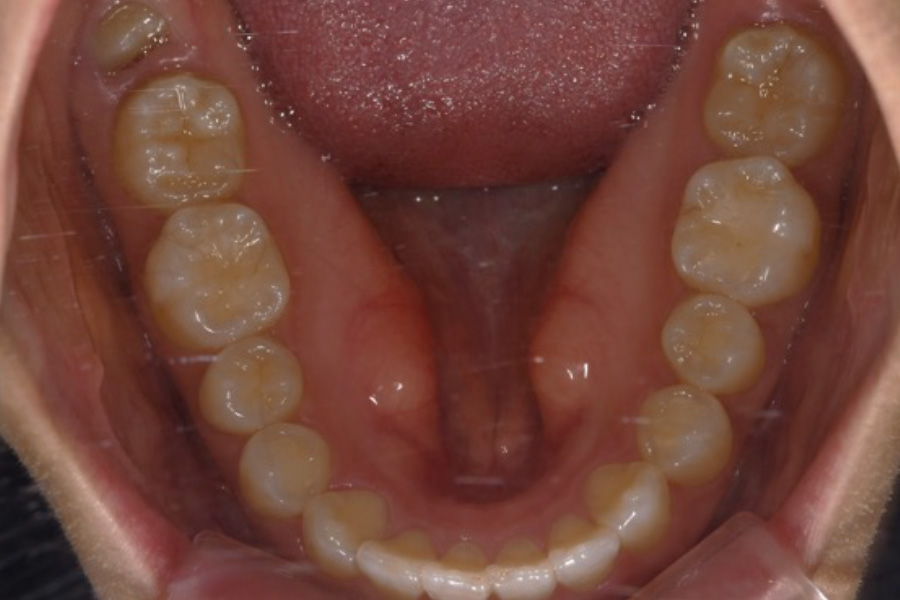

治療前

主訴 歯並びを治したい

期間 5か月

費用 マウスピース矯正(キャンペーン)

434,000円(税込)

治療内容 目立ちにくいマウスピース矯正(非抜歯矯正)

歯と歯の間に隙間をつくることにより、歯列弓を広げながら治療を行いました。